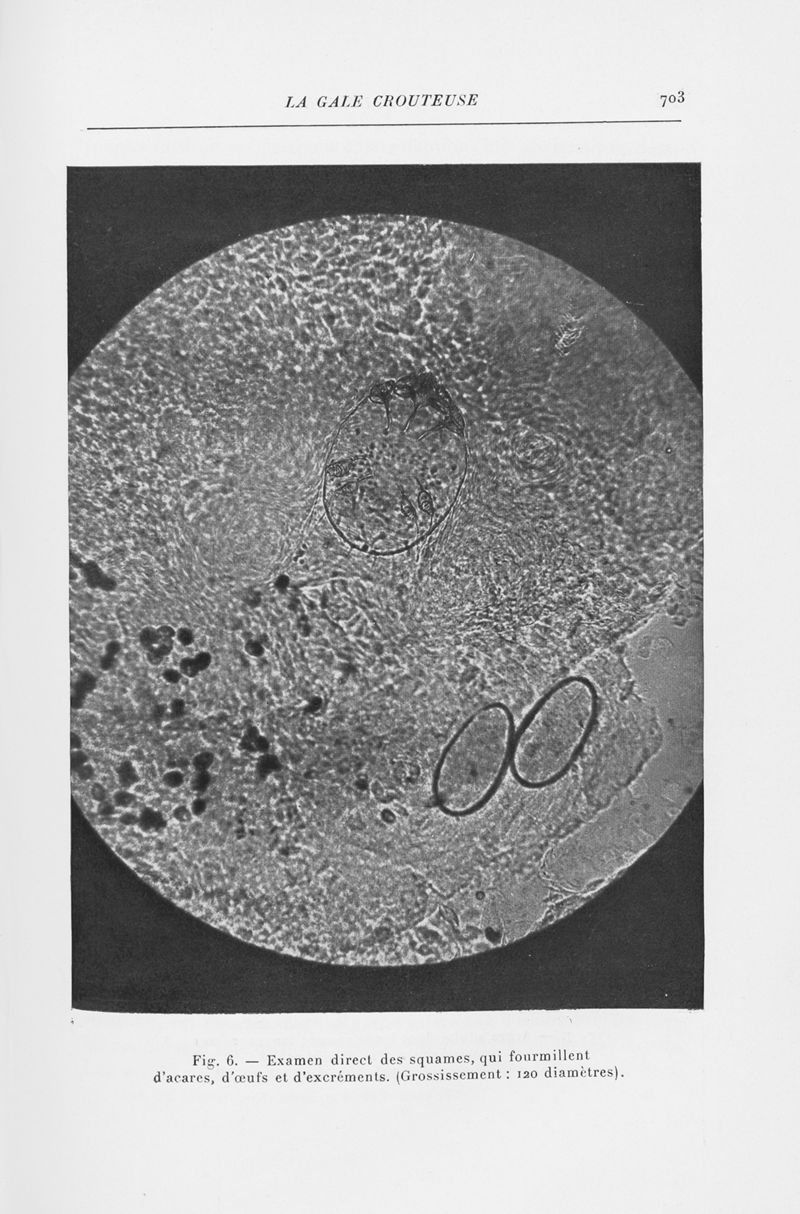

Annales de dermatologie et de syphiligraphie

7ème série, tome VI. - Paris : Masson, 1935.